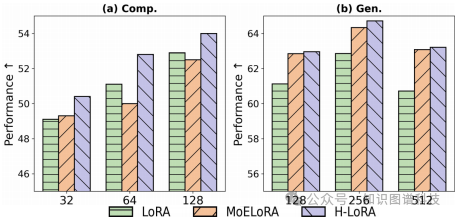

异构低秩适应(H-LoRA):H-LoRA通过低秩矩阵分解将理解和生成任务的异构知识存储在独立的模块中,并通过硬路由选择动态提取任务相关的知识。H-LoRA的计算开销较低,特别适用于大规模任务。

异构低秩适应(H-LoRA)技术通过低秩矩阵分解将理解和生成任务的异构知识存储在独立的模块中。具体实现过程中,H-LoRA将 bypass weight matrix分解为两个低秩矩阵,从而减少可学习参数的数量。H-LoRA的优势在于其较低的计算开销,特别适用于大规模任务。与混合专家(MoE)方法相比,H-LoRA通过矩阵合并和路由权重分配机制避免了多重矩阵乘法的延迟,显著提高了计算效率。